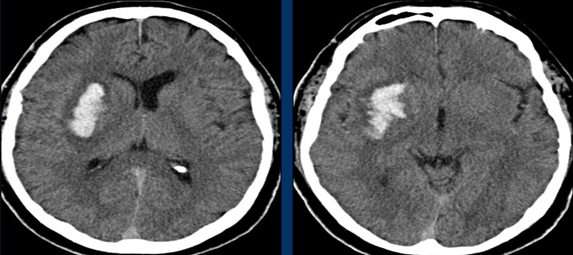

Xuất huyết não nhân bèo, thường gặp ở các bệnh nhân cao huyết áp.

Hình ảnh tăng tỷ trọng động mạch não giữa MCA bên trái, do huyết khối hoặc tắc mạch. Tương ứng với tắc MCA trên CTA.

Hình ảnh giảm tỷ trọng nhân bèo, thường liên quan đến nhồi máu động mạch não giữa MCA